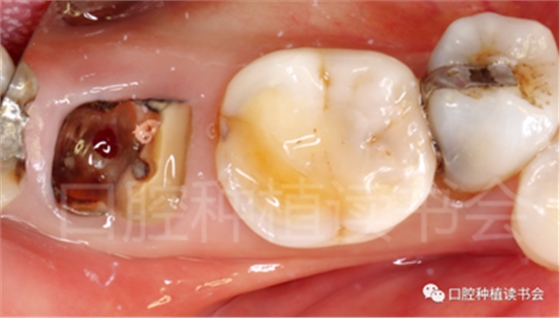

圖1 無法保留的上頜隱裂后牙,拔牙后即刻種植。

患者為70歲女性,右下后牙樁核冠因遠中牙根縱裂脫落,全身健康狀況良好,輕度骨質(zhì)疏松??趦?nèi)檢查:47殘根,遠中根縱裂,部分根面已腐至齦下2mm,叩(++),松(-);48近中傾斜阻生,咬合關系、修復間隙及牙周情況正常(圖12)。

圖12 遠中根縱裂及根面齲導致47殘根無法保留。